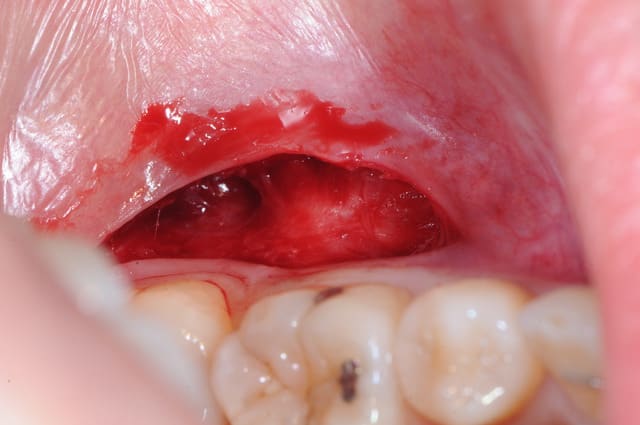

j'ai réalisé une exerèse d'un petit "fibrome" au niveau de la partie muqueuse de la lèvre mandibulaire, avec l'accord du dermato qui a vu les photos.

Dsc 0853 o2u5mi - Eugenol

Dsc 0855 vczury - Eugenol

Dsc 0856 zsy2pv - Eugenol

Dsc 0857 gmhyjs - Eugenol